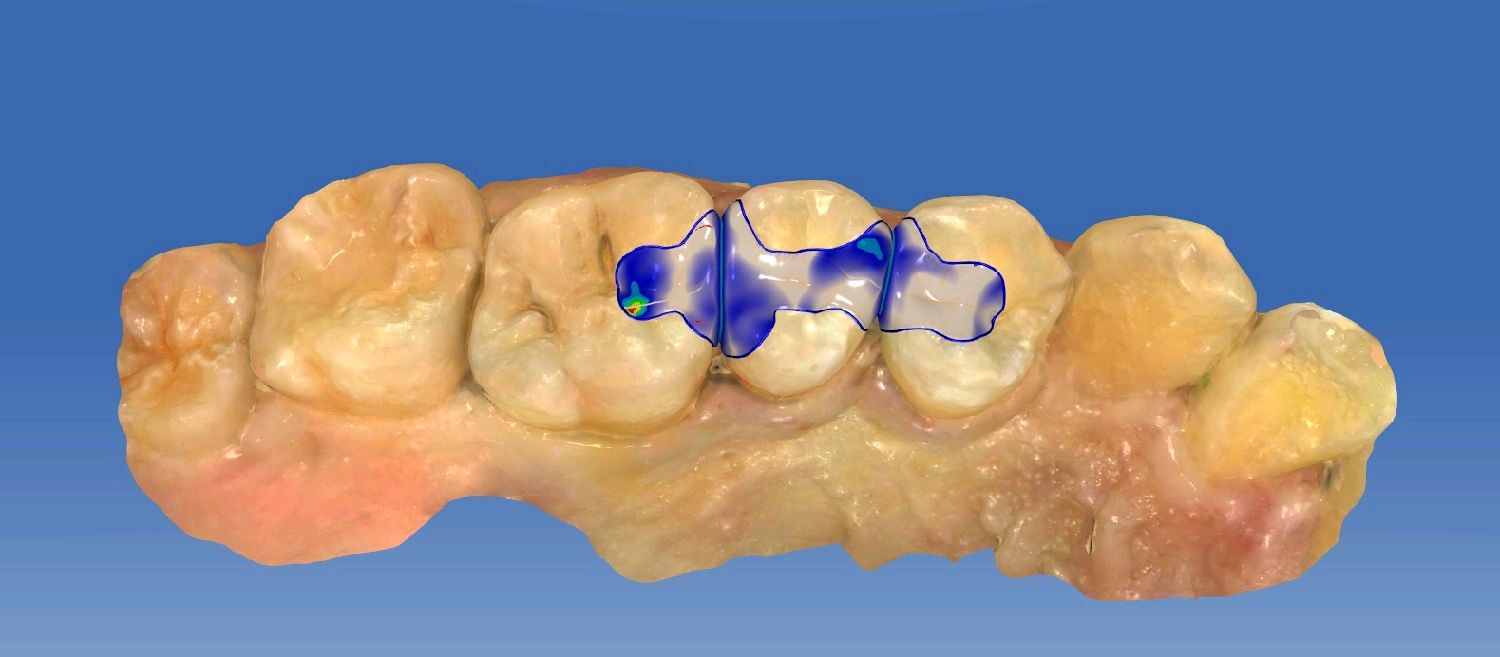

患者男24岁,自述右侧后牙食物嵌塞,无用牙线习惯。检查发现14,15,16,45,46 ,47邻颌面龋坏,探(-),扣(-),冷测正常,龋坏至牙本质中层,余无特殊。

治疗计划:嵌体修复

食物嵌塞为细菌提供了良好的滋生环境,容易导致细菌大量繁殖,产生酸性物质,从而增加蛀牙的风险。最好是用嵌体修复,能更好的恢复牙体的形态和功能。想要有一口好牙齿,做起来也不难。但是,单单口腔清洁这件小事,大多数人都没做好。你以为刷遍了牙齿的每个角落,但可能只刷了一半的牙。刷毛无法有效进入牙缝隙刷牙后仍有食物残渣等残留于牙齿邻面部位导致邻面龋坏。平时不易察觉,需要定期检查,为了更恢复邻接关系,预备制作嵌体,更好的恢复了牙体形态,增加了固位力,恢复正常的邻接关系,可以得到更好洁。基牙预备后,通过德国西诺德 CEREC ,当日完成即可佩戴,患者满意。